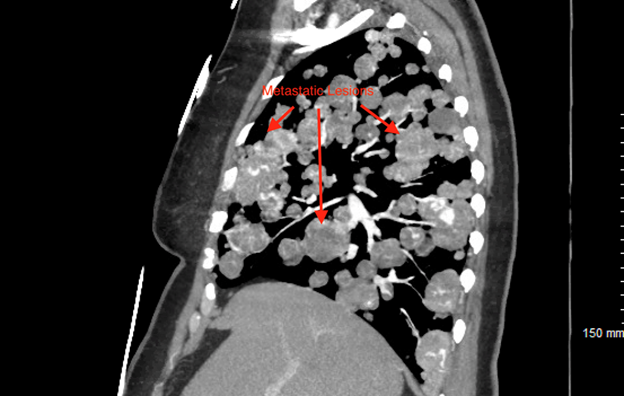

innumerable diffuse bilateral pulmonary metastatic appearing nodules with areas

of nodular conglomeration (Figures 2 and

Figure 3: Diffuse

Bilateral Pulmonary Metastatic Appearing Nodules with areas of Nodular

Conglomeration